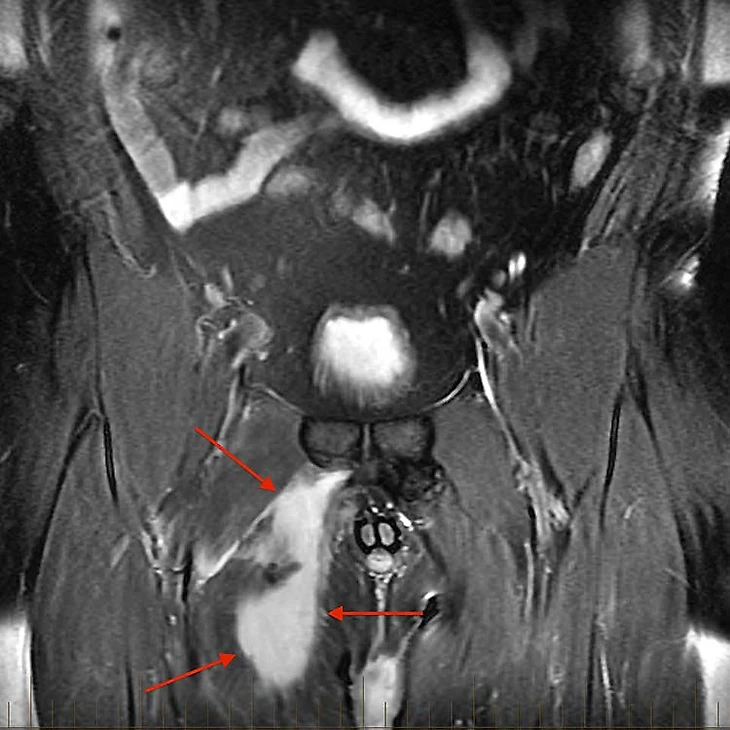

Если же методы выше не позволили поставить диагноз или оказались недостаточно точны, игрок отправляется на МРТ. Как правило, там мы видим отек или гематому в области повреждения мышцы, как на картинке ниже.

Источник: FIFA medical Network

Слева на снимке травмированное бедро, стрелками отмечена ярко белая область гематомы и отека. Такую картину мы увидим при относительно недавнем повреждении мышцы. Можете сравнить с симметричной областью справа. Четкий ход волокон серого цвета.

В этом случае следует пройти также и неврологическое обследование, потому что, как уже было сказано выше, в этой области проходят ветви запирательного и бедренного нерва, поэтому важно исключить их сдавление или травму. Особенно если клиническая картина не соответствует тому, что мы видим на снимках, или отсутствует какая-либо динамика.